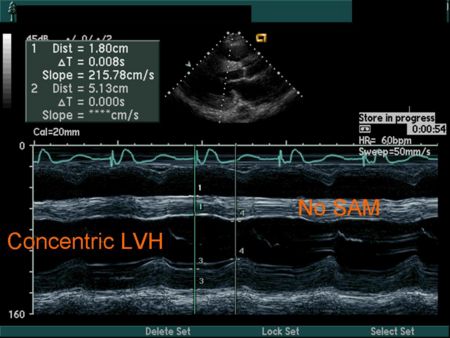

M Mode in Hypertrophic Cardiomyopathy

- Septal hypertrophy

- Systolic anterior motion (SAM) of the anterior mitral valve leaflet

Hypertensive Heart Disease

| |- |